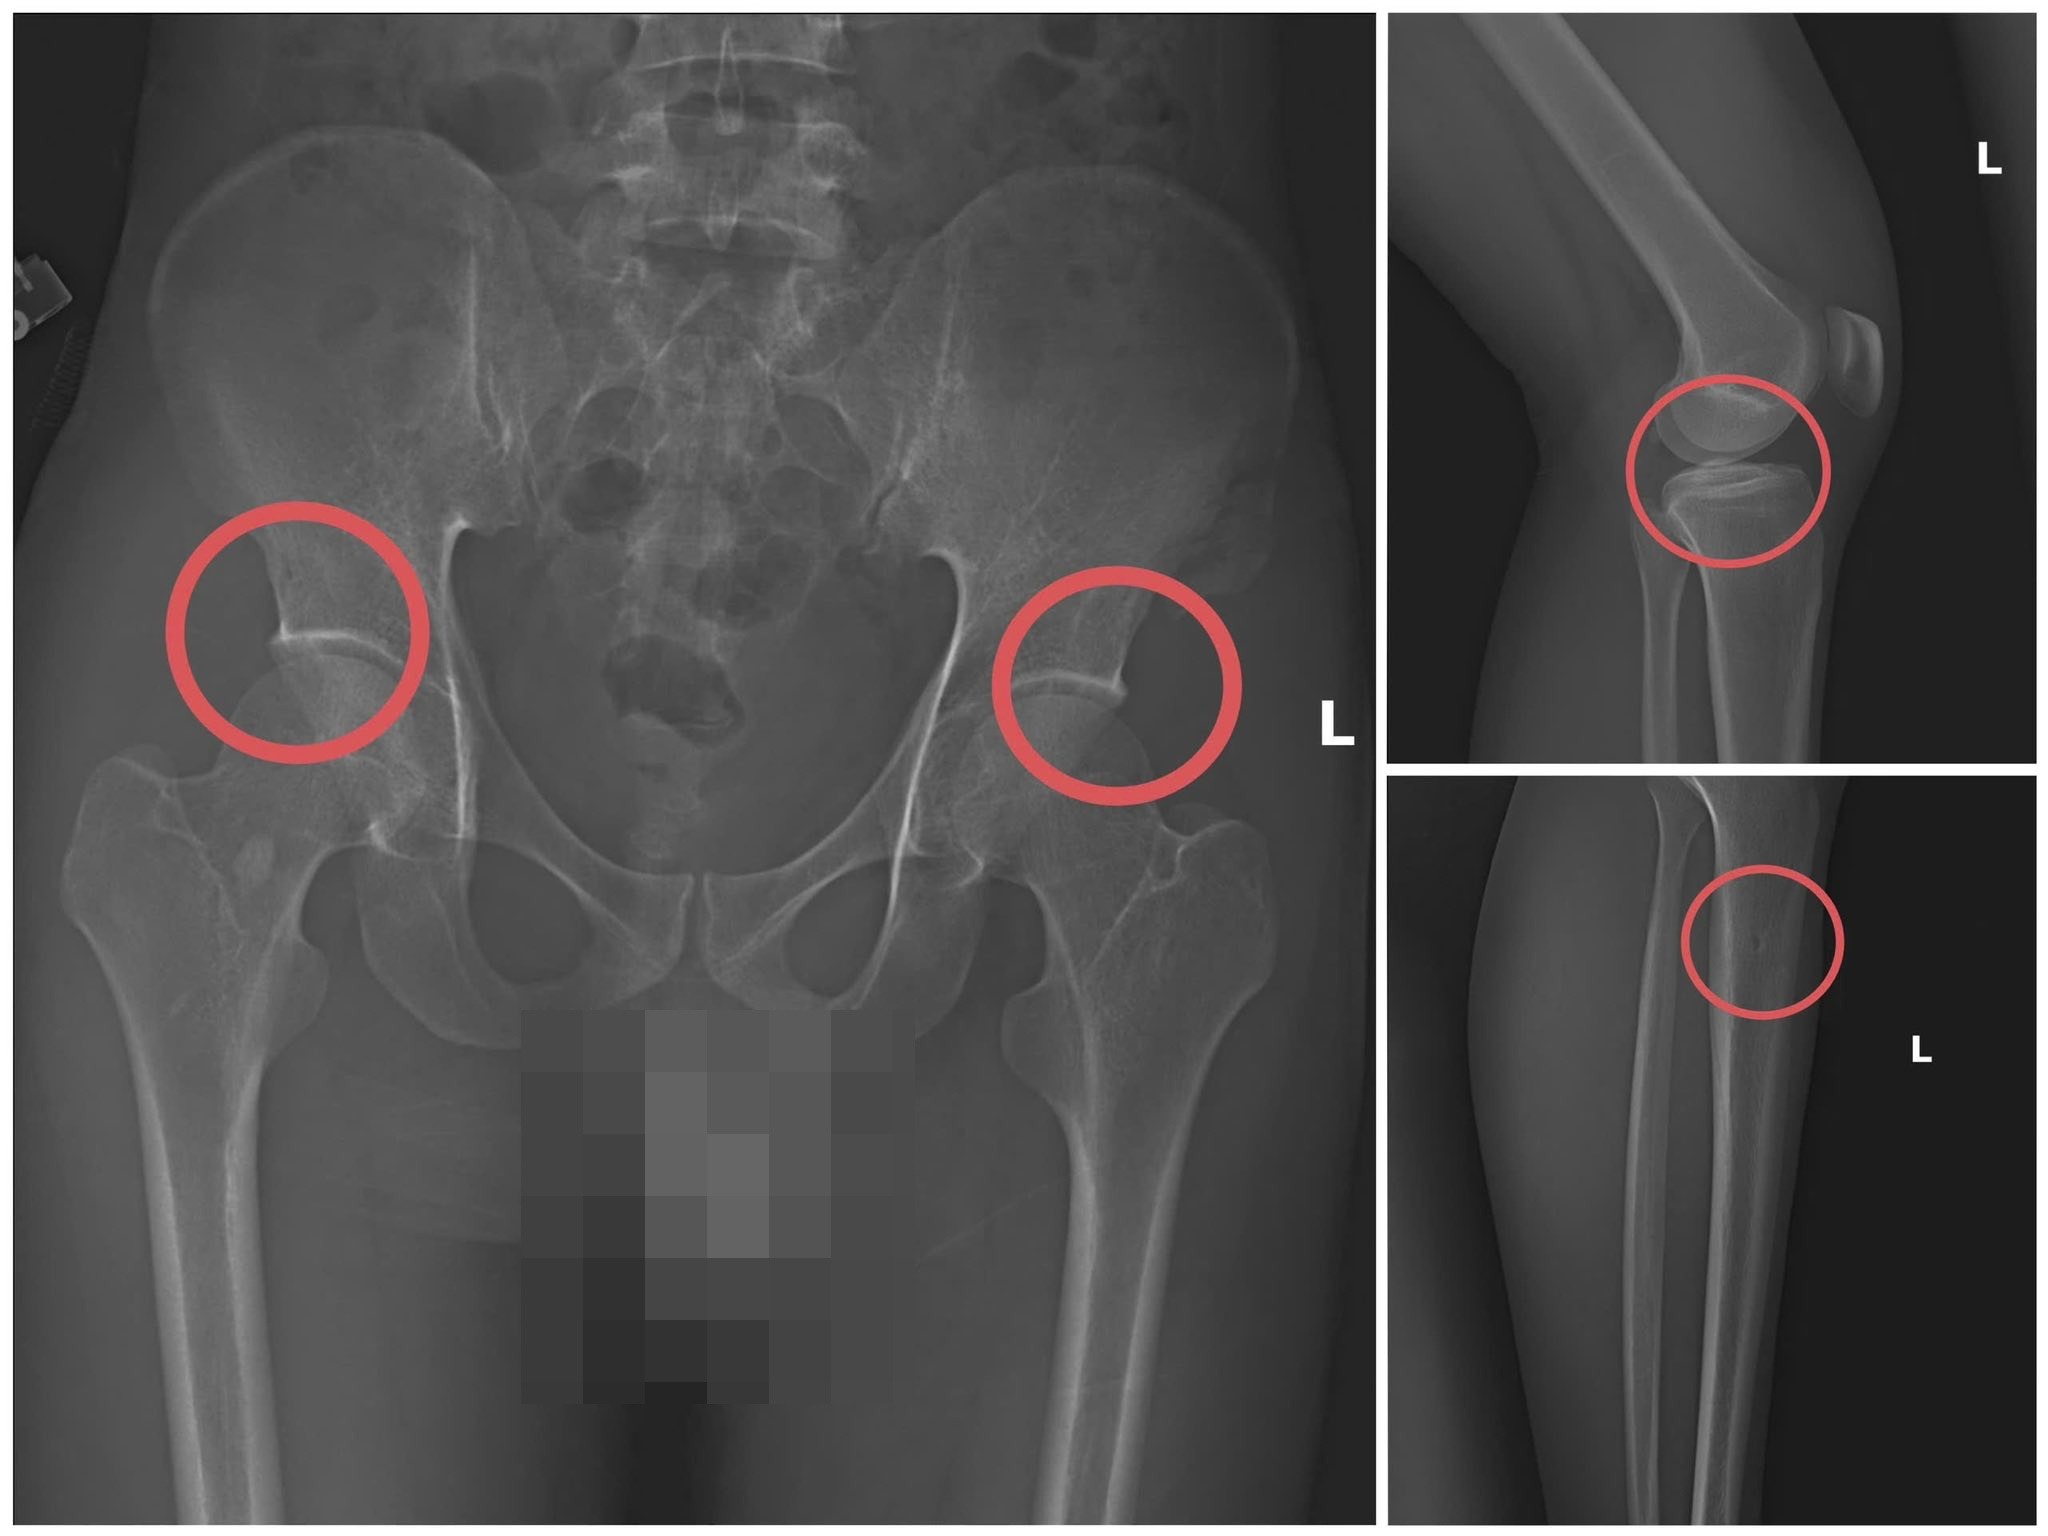

Hình ảnh xương khớp do Châu gây thương tích để chiếm đoạt tiền bảo hiểm nhân thọ - Ảnh: Công an tỉnh Phú Thọ |

Theo đó, thông qua các tài liệu thu thập được, cơ quan Cảnh sát điều tra làm rõ đối tượng Tạ Minh Châu (SN 1995, nguyên cán bộ Trung tâm Y tế huyện Cẩm Khê) là kẻ chủ mưu, cầm đầu. Lợi dụng thời gian dài công tác trong ngành y và am hiểu sâu cấu tạo xương – khớp, cũng như cơ chế chi trả bảo hiểm đối với các thương tích gãy xương giá trị cao, Châu đã dựng lên một quy trình trục lợi bài bản, từ việc vận động mua bảo hiểm, tổ chức gây thương tích, đến hợp thức hóa hồ sơ bệnh án để chiếm đoạt tiền của các công ty bảo hiểm.

Đáng chú ý, Châu trực tiếp thực hiện hành vi tiêm thuốc mê, rồi dùng kim tiêm, búa, đinh để tác động vào xương người mua bảo hiểm, tạo nên các vết nứt, vỡ xương tương tự tai nạn thật. Khi thương tích đã tạo xong, Châu tiếp tục hướng dẫn các đối tượng dựng hiện trường giả như điện giật ngã, trượt chân ngã suối nhằm hợp thức hóa bệnh án và hoàn thiện hồ sơ yêu cầu chi trả.

Theo đánh giá của Giám đốc Công an tỉnh Phú Thọ, thủ đoạn này vừa tàn nhẫn, vô nhân tính, coi thường sức khỏe, tính mạng của người tham gia, vừa được tính toán kỹ để gây thương tích đúng vị trí có mức chi trả cao, khiến các công ty bảo hiểm khó phát hiện dấu hiệu gian dối.

Với thủ đoạn trên, các đối tượng đã chiếm đoạt hơn 6 tỷ đồng từ nhiều công ty bảo hiểm nhân thọ như Manulife, AIA, Dai-ichi Life, FWD, Sun Life, Chubb Life… riêng Công ty Manulife bị chiếm đoạt 2,6 tỷ đồng.